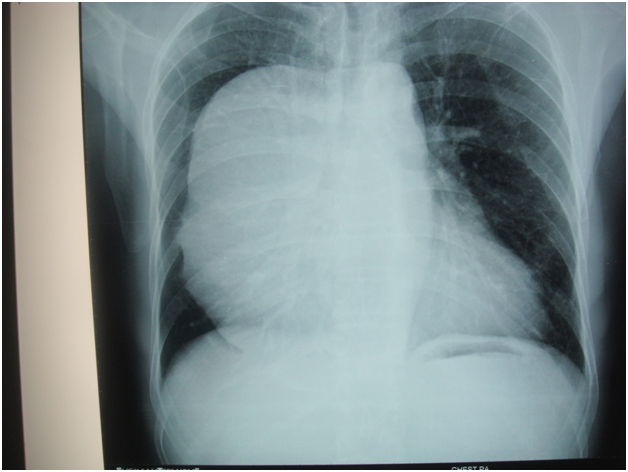

Figure 1 Posterior mediastinal myxoid liposarcoma.

Figure 2 Huge mediastinal tumour ---teratoma compressing both lungs and heart below.